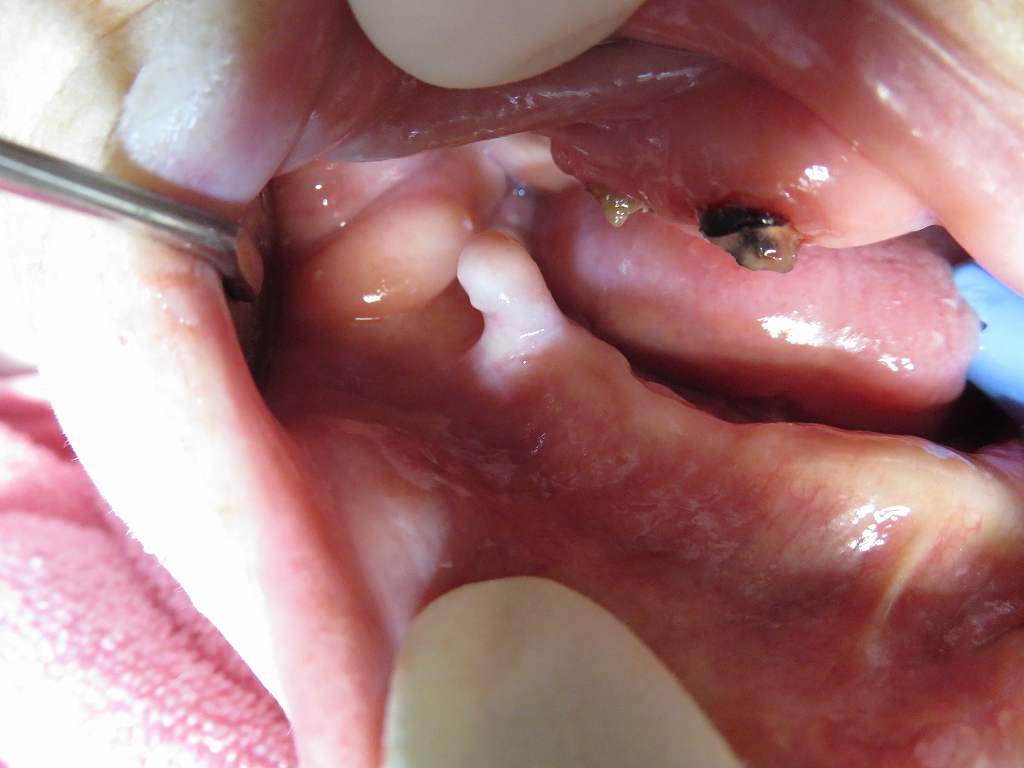

訪問歯科で往診で回っていると様々なことに出会います|お知らせ |広島市安佐南区の歯科医院 訪問歯科で往診で回っていると様々なことに出会います トップ お知らせ・ブログ お知らせ 訪問歯科で往診で回っていると様々なことに出会います 訪問歯科で往診で回っていると様々なことに出会います 右下奥の歯茎に歯ではないですが、歯肉に覆われた骨隆起に出会いました これが骨隆起です この方は入れ歯をしてはいない方でしたが、、、 入れ歯が必要で使っている頃では、 これはかなり障害があったのでは? 上戸の対咬関係もこのような状態になります レントゲンで調べると歯ではなく確かに骨で間違いがないようです Web診療予約 初めての方へ 選ばれ続ける理由 院内設備について 歯が痛いしみる一般歯科 歯がぐらぐらする歯周病 健康な歯を保ちたい予防歯科 子供の虫歯予防をしたい小児歯科 銀歯をセラミックに審美歯科 白い歯を目指しませんか?ホワイトニング 矯正専門医がいるので安心矯正歯科 抜けた歯を補いたいインプラント・入れ歯 医院案内 スタッフ紹介 メリィハウス歯科クリニックオフィシャルホームページ ラベンダー歯科クリニックオフィシャルホームページ お知らせ・ブログ ホーム 診療科目 一般歯科 歯周病治療 予防治療 小児歯科 審美治療 ホワイトニング 矯正歯科 入れ歯・インプラント マウスピース矯正 初めての方へ 院長・スタッフ 設備紹介 医院案内・アクセス メニューを閉じる